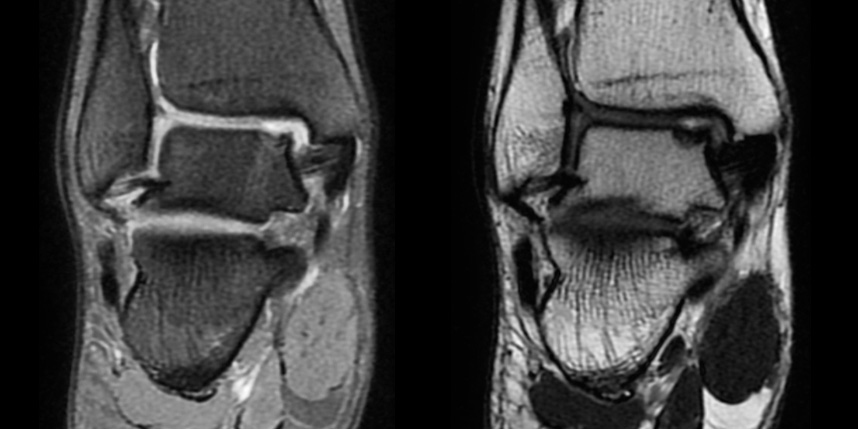

환자 자신의 건강한 연골을 채취하여 손상된 부위에 이식하는 방법으로, 발목 연골 손상에 주로 이용하며 정상 연골을 채취해야 하기 때문에 공여부(donor site)의 문제가 있을 수 있다는 점이 최대 단점입니다.

타병원 미세천공술 실패 후 통증으로 내원하신 사례

* 환자에게 받은 소중한 자료입니다.